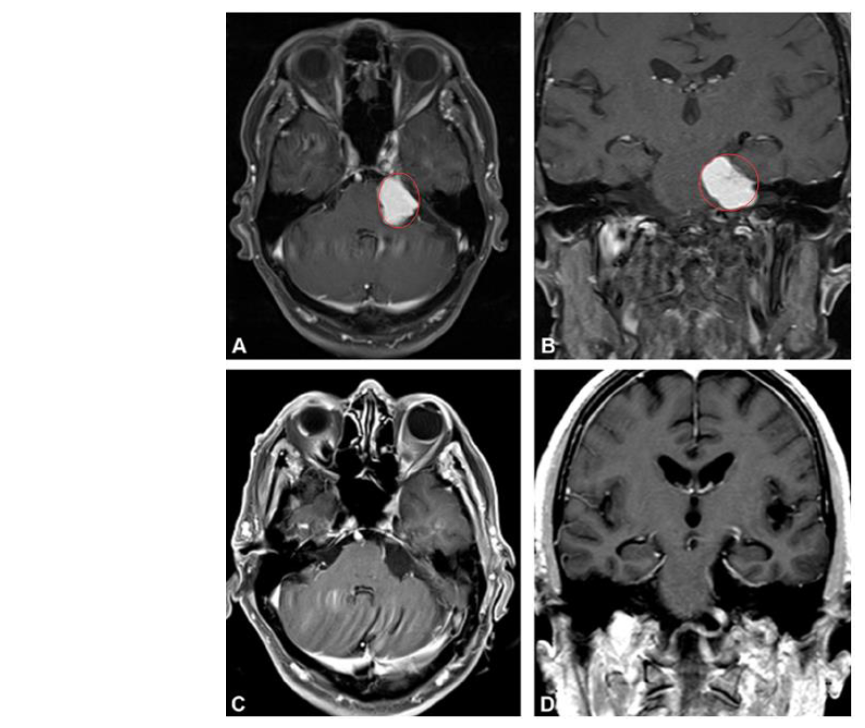

81岁老人全切手术前后对比

一位81岁的老人因左侧面部麻木和步态失衡3个月,去医院检查出“左侧桥小脑角区占位”。

术前MRI:从脑幕下表面向左小脑桥脑角产生大的均匀增强病变,引起的脑干压缩,出现面部麻木和步态失衡

诊断:桥小脑角区脑膜瘤

术后情况:手术顺利,脑膜瘤得以全切,没有新的术后神经功能缺损,脑干压迫消失。术后4天出院回家,术后1个月,步态失衡和左侧面部麻木消失。其后的4年间,老人生活正常。